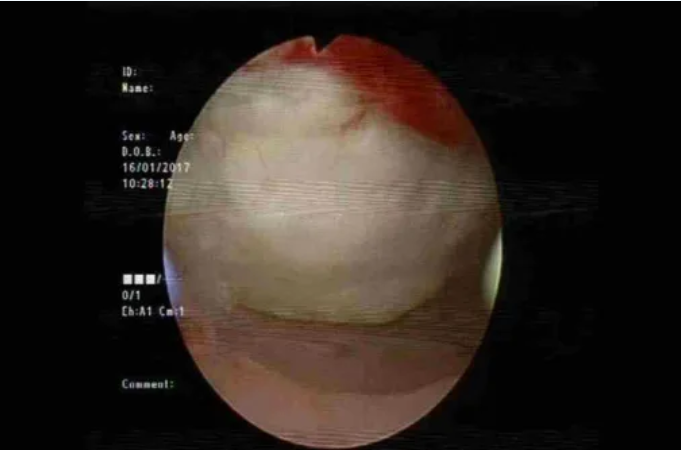

图:宫腔镜显示HIFU造成的子宫内膜损伤(本图由北京复兴医院马宁教授提供)